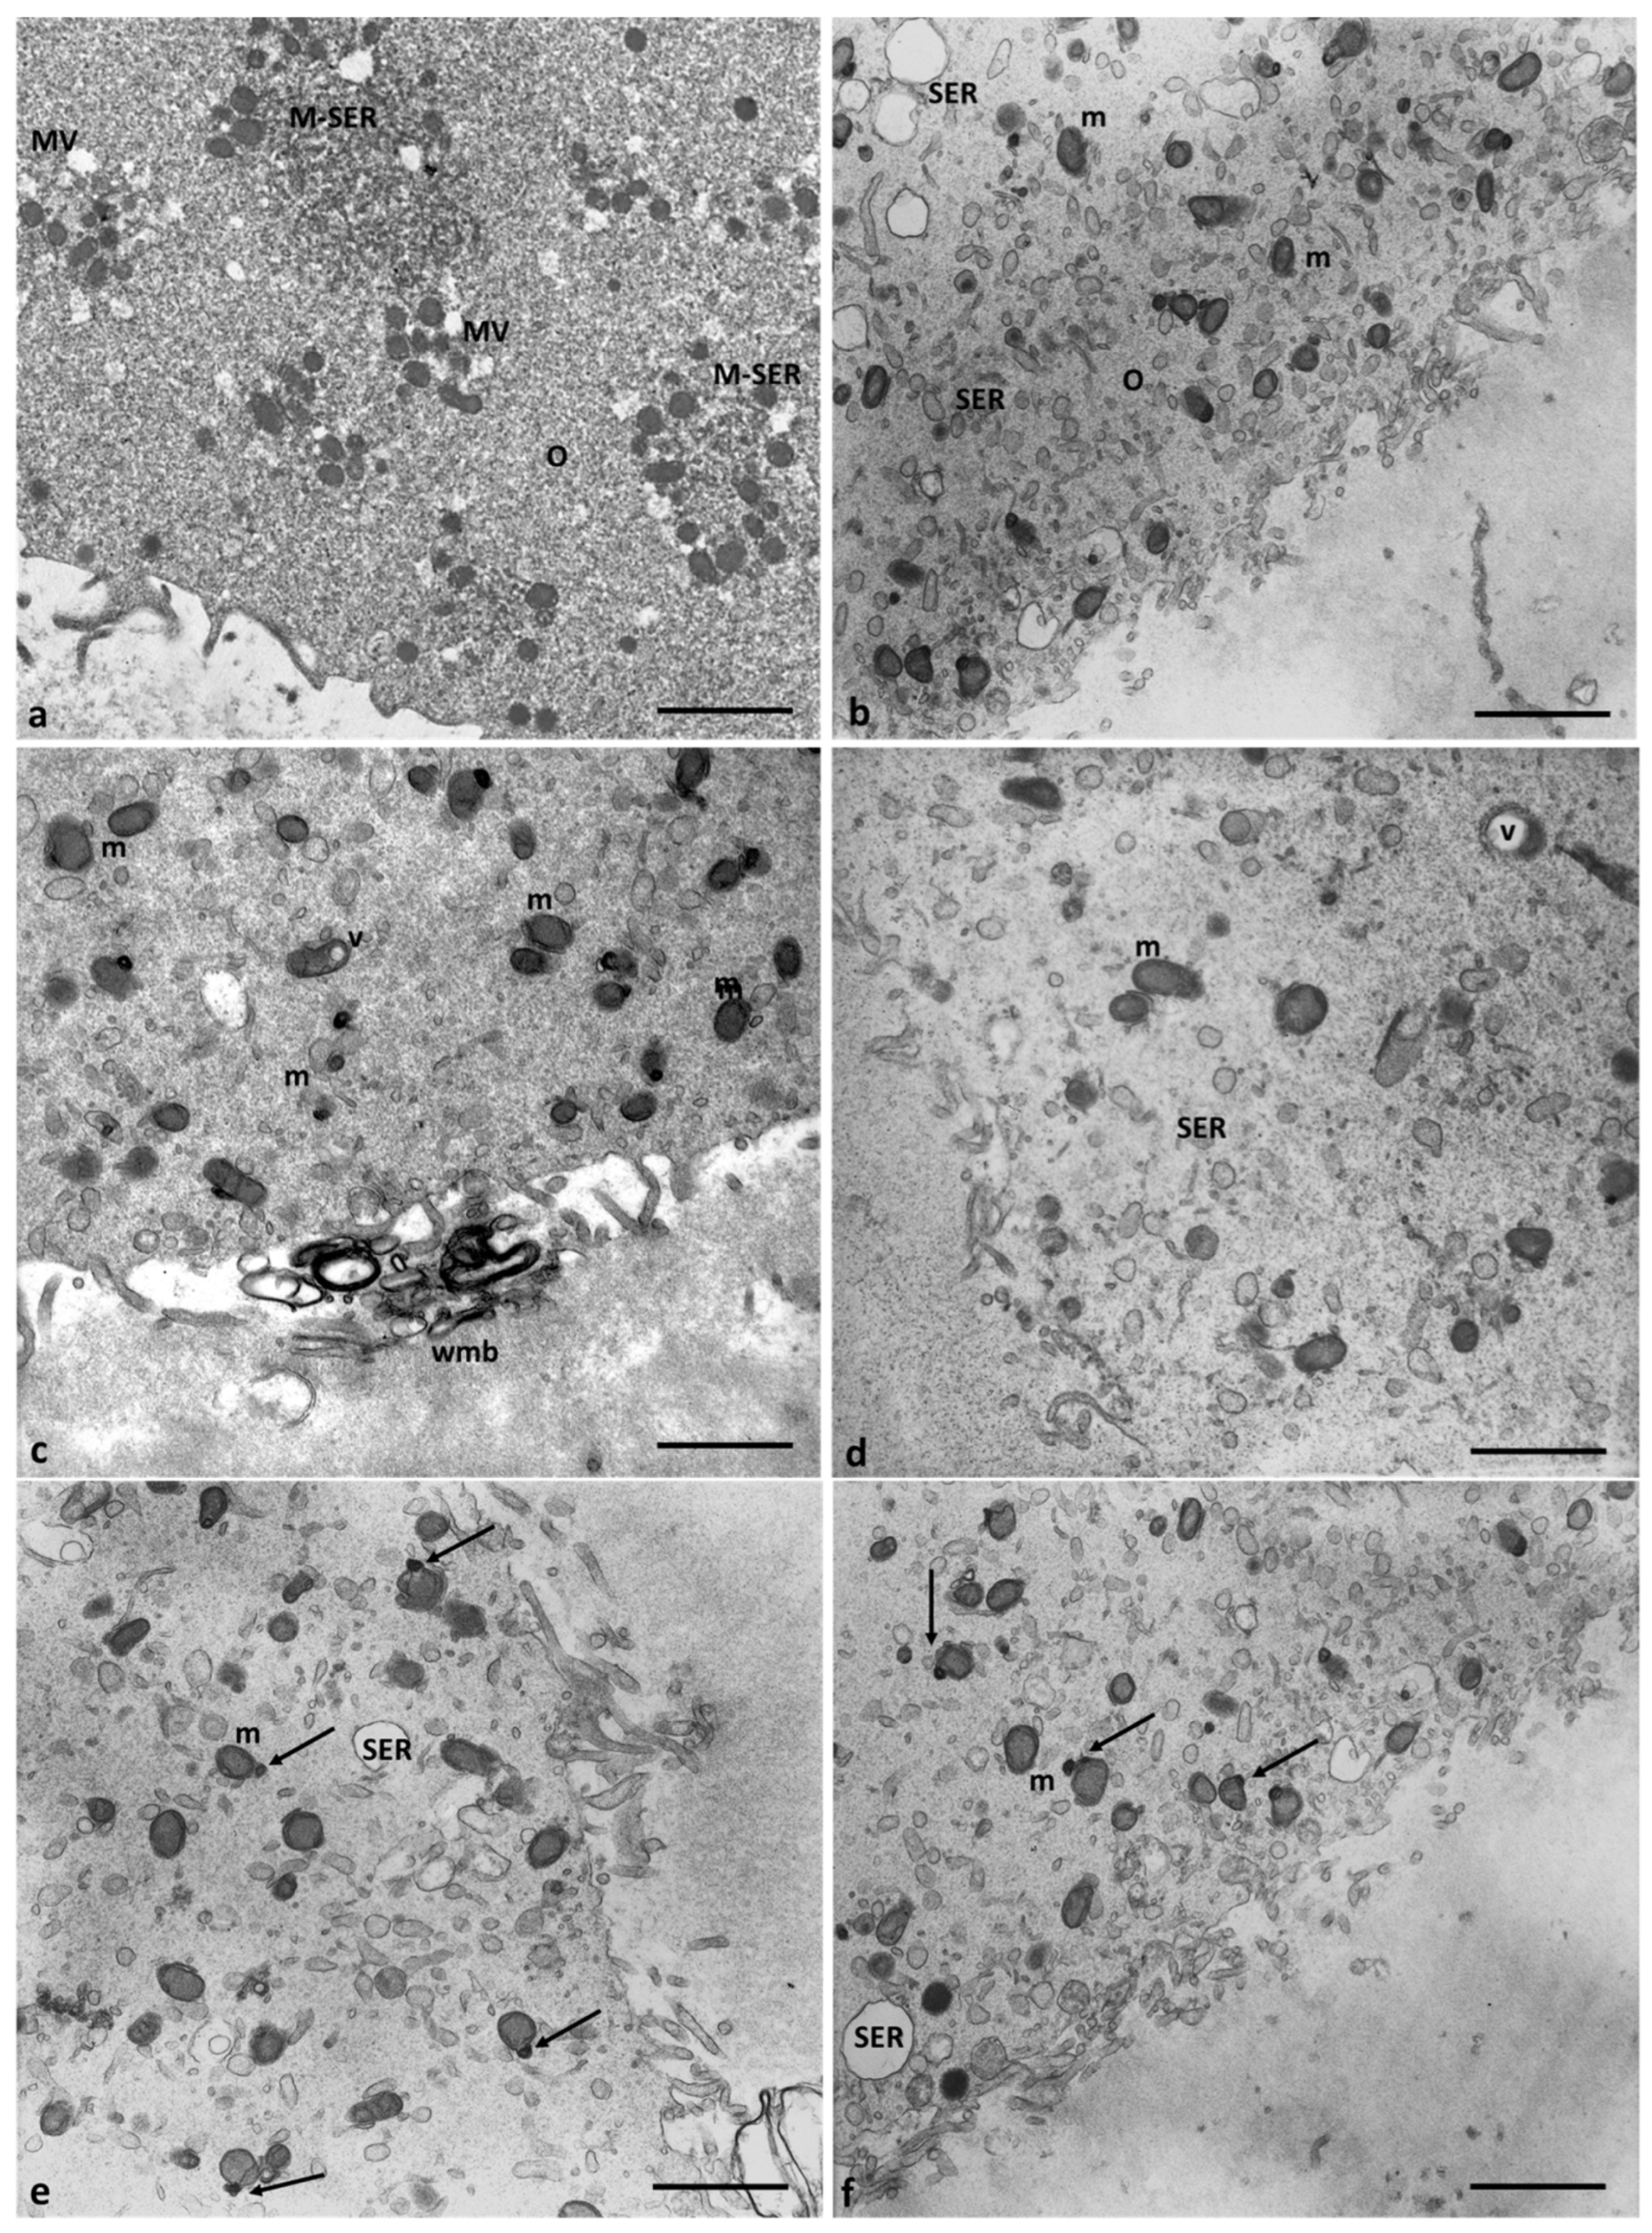

Since CCs closely interact with the oocyte not only after natural ovulation or follicle aspiration but also during and after fertilization, influencing various changes necessary for implantation and early development of the zygote, the study of possible Cd-induced morphological alterations was extended to these cells. A distinctive characteristic of CCs is their capacity to change from a compact cell mass around the oocyte into a dispersed structure of cells during the preovulatory period, a process called cumulus expansion that involves the synthesis and deposition of a mucoid fibrillar intercellular matrix.

The ultrastructural analysis was focused only on the corona cells and clusters of the outer CCs, although these were slightly reduced in number due to unavoidable mechanical manipulation of the COCs [25,26].

Figure 8 shows the cytoplasmatic ultrastructure of CCs of Group 1 patients, attesting to the typical steroidogenic features of these cells. CCs appeared irregularly rounded, with an oval nucleus eccentrically located showing dispersed chromatin (Figure 8a); they also contained many types of organelles such as mitochondria with lamellar or tubular cristae, abundant membranes of SER, microtubules, microfilaments in close contact with SER elements, and abundant lipid droplets. The latter were also associated with mitochondria and SER membranes. Micro-peroxisomes, cisternae of rough endoplasmic reticulum (RER), ribosomes, vesicles, membranes belonging to the Golgi complex, and polyribosomes were also present in the cytoplasm (Figure 8b).

Figure 8.

Cumulus cell ultrastructure of Group 1 patients. (a) Overview of the cell with a large, eccentric, and oval nucleus and numerous cytoplasmic organelles. (b) Detail of different types of organelles in the cytoplasm. LD, lipid droplets; SER, smooth endoplasmic reticulum; RER, rough endoplasmic reticulum; G, Golgi apparatus; m, mitochondria; r, ribosomes; pl, polyribosomes; p, micro-peroxisome. Bar = 30 µm (a); Bar = 12 µm (b).

In 71.4% of the Group 2 patients (5/7), the CCs appear with moderate electron density, dispersed within a fine and delicate fibrillar extracellular matrix, irregularly rounded, polyhedral, or elongated in shape (Figure 9a), with large and short cytoplasmic processes projecting through the ZP that did not seem to reach and contact oocyte microvilli (Figure 9b). The shape of nuclei changed from oval to flattened and indented (Figure 9c, thin arrow, and Figure 10b), and abundant glycogen granules were detected, dispersed in the cytoplasm, and around numerous and large lipid droplets. Micro-peroxisomes, organelles that confer the steroidogenic ability to these cells, have not been observed.

Figure 9.

Morphological changes in the shape of CCs of Group 2 patients. (a) CCs dispersed within the extracellular matrix, with a shape irregularly rounded, polyhedral, or elongated, and some cells showing characteristic signs of apoptosis (thick arrows). (b) CCs with large cytoplasmic processes projected in the ZP. (c) cell nuclei appear flattened and indented (thin arrows), and (d) abundant granules (g) of glycogen appear dispersed in the cytoplasm, around lipid droplets, and inside vacuoles. Bar = 180 µm (a); Bar = 90 µm (b); Bar = 70 µm (c); Bar = 40 µm (d).

Figure 10.

Accumulation of glycogen in CCs of Group 2 patients. (a,b) Abundant granules of glycogen (g) appear dispersed in the cytoplasm and (b,c) around lipid droplets (LD). Bar = 25 µm (a–c); Bar =18 µm (d).

In 28.6% of the Group 2 patients (2/7), CCs showed even characteristic apoptotic signs (Figure 9a, tick arrows, and Figure 11).

Figure 11.

Regressing and degenerating CCs in Group 2 patients. (a–c) Numerous vacuoles (V) and autophagosomes (A) containing involuting organelles occur in the cytoplasm. Note the presence of abundant glycogen granules (g) peripherally accumulating around the nucleus (N) or inside vacuoles, cytoplasmic fragments, and cellular blebs. (d) Evidence of cytoplasmic lysis and vacuolization. Nuclear alterations occur (arrows). m, mitochondria; LD, lipid droplets. Bar = 35 µm.

Figure 10 highlights details of the presence of abundant glycogen granules in the CCs of Group 2 patients. They were distributed particularly in the cytoplasm, close to nuclear indentations (Figure 10a,b, arrows), around lipid droplets (Figure 10c,d), which indicates a possible impairment of the metabolism of carbohydrates and glucose homeostasis.

Figure 11 shows degenerating CCs in Group 2 patients. Numerous regressing elements such as vacuoles of different sizes and autophagosomes containing glycogen granules and involuting mitochondria are present (Figure 11a–c); cytoplasmic fragments deriving from cellular blebbing (Figure 11c), pyknotic (Figure 11c) or regressing nuclei (Figure 11a–c), and a dense or lysed, vacuolized cytoplasm (Figure 11d) were observed.